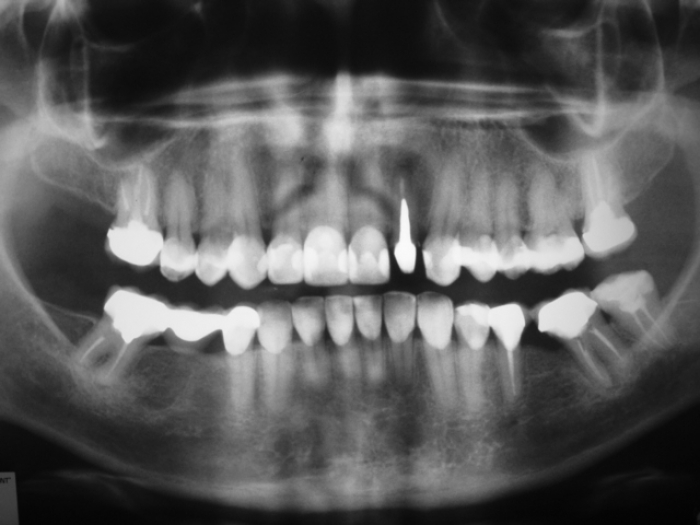

Raio X com prótese fixa em porcelana sobre implante Cone Morse